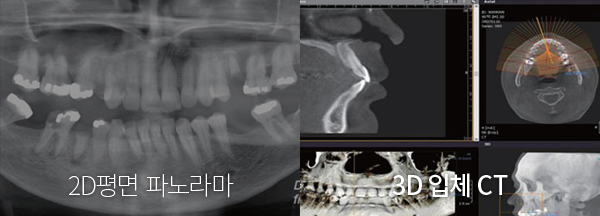

÷´Ü µðÁöÅÐ ¹æ½ÄÀÔ´Ï´Ù.

ÆÄ³ë¶ó¸¶ X-ray ÃÔ¿µÀ¸·Î´Â 2Â÷¿øÀûÀΠȯÀÚÀÇ Ä¡¾Æ »óŸ¸ È®ÀÎÇÒ ¼ö ÀÖ¾î ÀÓÇöõÆ® ½Ã¼ú °èȹÀ» Á¤È®È÷ ÇÒ ¼ö ¾ø½À´Ï´Ù. ÄÄÇ»ÅÍ ºÐ¼®À» Ȱ¿ëÇÑ ÀÓÇöõÆ®´Â ÃÖ÷´Ü µðÁöÅÐ ¹æ½ÄÀ¸·Î 3Â÷¿ø CT ÃÔ¿µÀ» ÅëÇØ ȯÀÚÀÇ °ñÁ¶Á÷, ÁÖº¯Ä¡¾Æ¿ÍÀÇ °Å¸®, °¢µµ, ½Å°æ À§Ä¡ µîÀÇ Á¤º¸¸¦ ÅëÇØ Á¤È®ÇÑ ½Ã¼ú °èȹÀÌ °¡´ÉÇÕ´Ï´Ù.